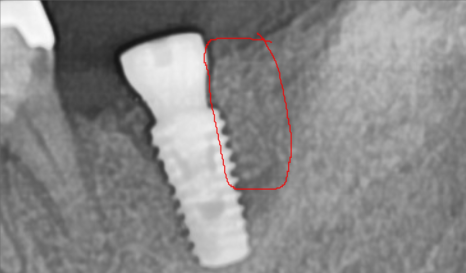

자세히 보는 작은 X-ray를 추가로 촬영합니다.

흠.. 생각보다 더 많이 심각한 상태입니다.

특히나 뿌리만 남은 치아는 내부에 골소실이 심각한 상태입니다.

한쪽은 치아 머리가 깨져서 검게 뿌리만 남아있고,

한쪽은 뿌리쪽에서 고름주머니가 잡혀있어

건들면 아프고, 매번 안좋은 냄세가 난다고 하시네요.

(촉감이 몰캉몰캉하니 고름이 차있는 상태입니다)

오래전 시행됬을 신경치료의 흔적이 보입니다..

아마 신경치료 후 크라운을 씌우셨을텐데

내부에 충치가 생겨 크라운이 머리채로 부러져나가버렸습니다.

이정도로 치아가 남지 않은 상태면 임플란트 이외에는 방법이 없습니다.